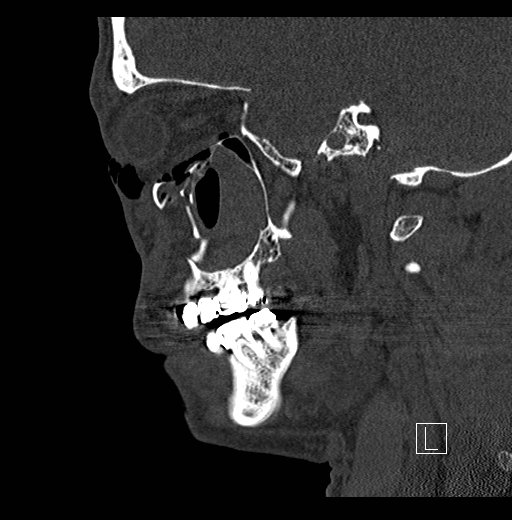

Physical exam showed marked left palpebral subcutaneous crepitus, as well as bulbar and palpebral conjunctival bulging. Visual acuity was normal with intact extraocular movements, and normal pupillary exam. Computed tomography (CT) imaging of the face was obtained and revealed multiple displaced fractures involving the left orbital floor and zygomatic arch associated with moderate periorbital and postseptal extraconal gas, resulting in orbital proptosis.